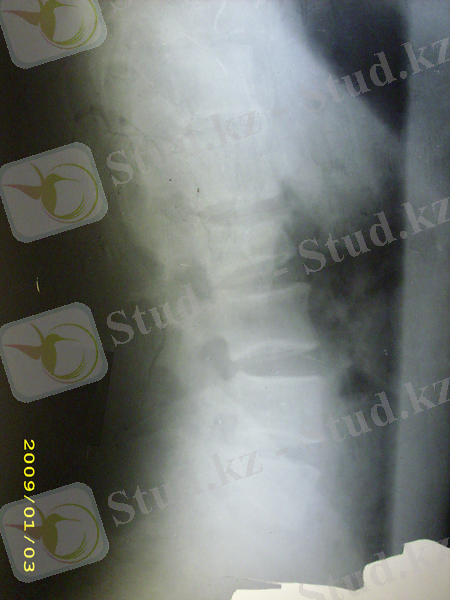

Радиологиялық зерттеулер. Тексеруді көрсеткіш екі проекциялы ретгенннен бастайды, алдыңғы артқы және бүйір, рентгенограмманың ортасында клинасмен анықталған зақымданған ошақ орналасады. Алдынғы артқы проекцияда көлденең өсінділер зақымдануы, омыртқалардың бүйірлык шығулары, ал қалған сынықтар бүйір проекцияда жақсы көрінеді. Әдеттегі сынықтардардың орнын білу кезінде рентгенологиялық тексеру барысында барлық кеуде бел ауысуын (бел омыртқаларының сынығына күдіктенгенде ) және мойын- кеуде ауысуында төменгі мойын омыртқаларының сынығын анықтағанда, науқас қолы төменге қарай, иық және иықүсті буының төмен түсіру арқылы рентген суретін жасаймыз. Рентгенограмманы бағалаған соң, керек жағдайда томограммыа, қиғаш проекциялы рентгенограмма, жасауға болады, Омыртқаның шығуы болатын болса, жоғары орналасқан омыртқа шыққан деп есептеледі. (рис. 5 а, б)

Омыртқа денесінің сынығының рентгендік көрінісі ретінде бүйір проекциядағы сына тәрізді деформация болып табылады. (рис. 5, в) .

Рис. 5. омыртқа зақымлдануы кезінде рентегн зерттеуі.

а -С3 омыртқасының алдыға қарай шығуы, б - С5омыртқасының малдыға шығуы, в - компрессионный перелом II L2 омыртқа денесінің II дәрежелі компрессиялы сынығы